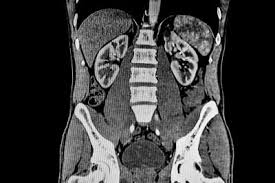

Investigaciones financiadas por los NIH sugieren que una herramienta impulsada por IA podría agilizar los diagnósticos y revelar marcadores tempranos de enfermedades crónicas

La TC es una forma común de imagen médica, que a menudo se realiza en la fase inicial de las evaluaciones médicas. Para obtener un diagnóstico, un radiólogo debe interpretar los resultados y, a menudo, también se necesitan pruebas adicionales y evaluaciones clínicas. Al principio, este proceso es largo y se vuelve aún más engorroso si se tiene en cuenta la creciente escasez <https://pubmed.ncbi.nlm.nih.gov/32029001/> de médicos en Estados Unidos.

Para preparar a Merlin para la amplia variedad de tareas, los investigadores inicialmente lo dirigieron a su archivo de datos clínicos, que conectaba más de 15.000 tomografías abdominales 3D junto con sus informes radiológicos y casi un millón de códigos diagnósticos. Utilizando esta información como material de estudio, Merlín aprendió sobre las relaciones entre los datos visuales y los escritos.

Los investigadores luego interrogaron a Merlin sobre más de 50.000 tomografías abdominales inéditas — procedentes de uno de cuatro hospitales diferentes — para conocer hasta qué punto su modelo podría coincidir con las conclusiones producidas por humanos asociadas a cada exploración.

De media, en 692 códigos diagnósticos diferentes, Merlin predijo con éxito cuál de dos escaneos tenía más probabilidades de estar asociado a un código particular durante el 81% de las veces, superando a varias variantes de otros dos modelos. Para un subconjunto de 102 códigos, el rendimiento de Merlin subió al 90%.

Los autores del estudio encontraron que, al comparar escáneres de diferentes sujetos, Merlin pudo identificar pacientes con mayor riesgo de desarrollar una enfermedad concreta en los próximos cinco años el 75% de las veces, frente al 68% del otro modelo. Estos hallazgos sugieren que el modelo puede detectar características clave en los escaneos que podrían perderse para el ojo humano, lo que sugiere que la herramienta podría ayudar a identificar nuevos biomarcadores para enfermedades, explicó Blankemeier.

Los investigadores aumentaron aún más la dificultad desafiando a Merlin a interpretar las tomografías computarizadas del tórax, una parte del cuerpo completamente ausente del material de estudio de la TC. La capacidad única de Merlin para identificar características generalizables de la enfermedad le permitió rendir tan bien o mejor que los modelos entrenados exclusivamente con escáneres de tórax.